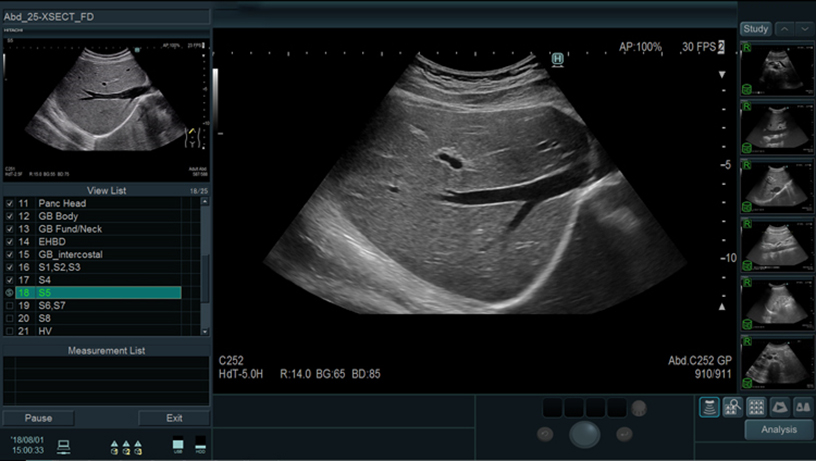

Prior fixed examination protocols and imaging conditions can be registered. Button operations can be reduced significantly to support efficient examinations. Additionally, a reference image can be displayed via the "Guide View" function.